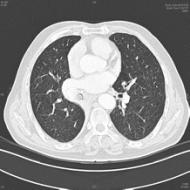

图为长在患者支气管里的肺错构瘤

图片由牟向东主任提供